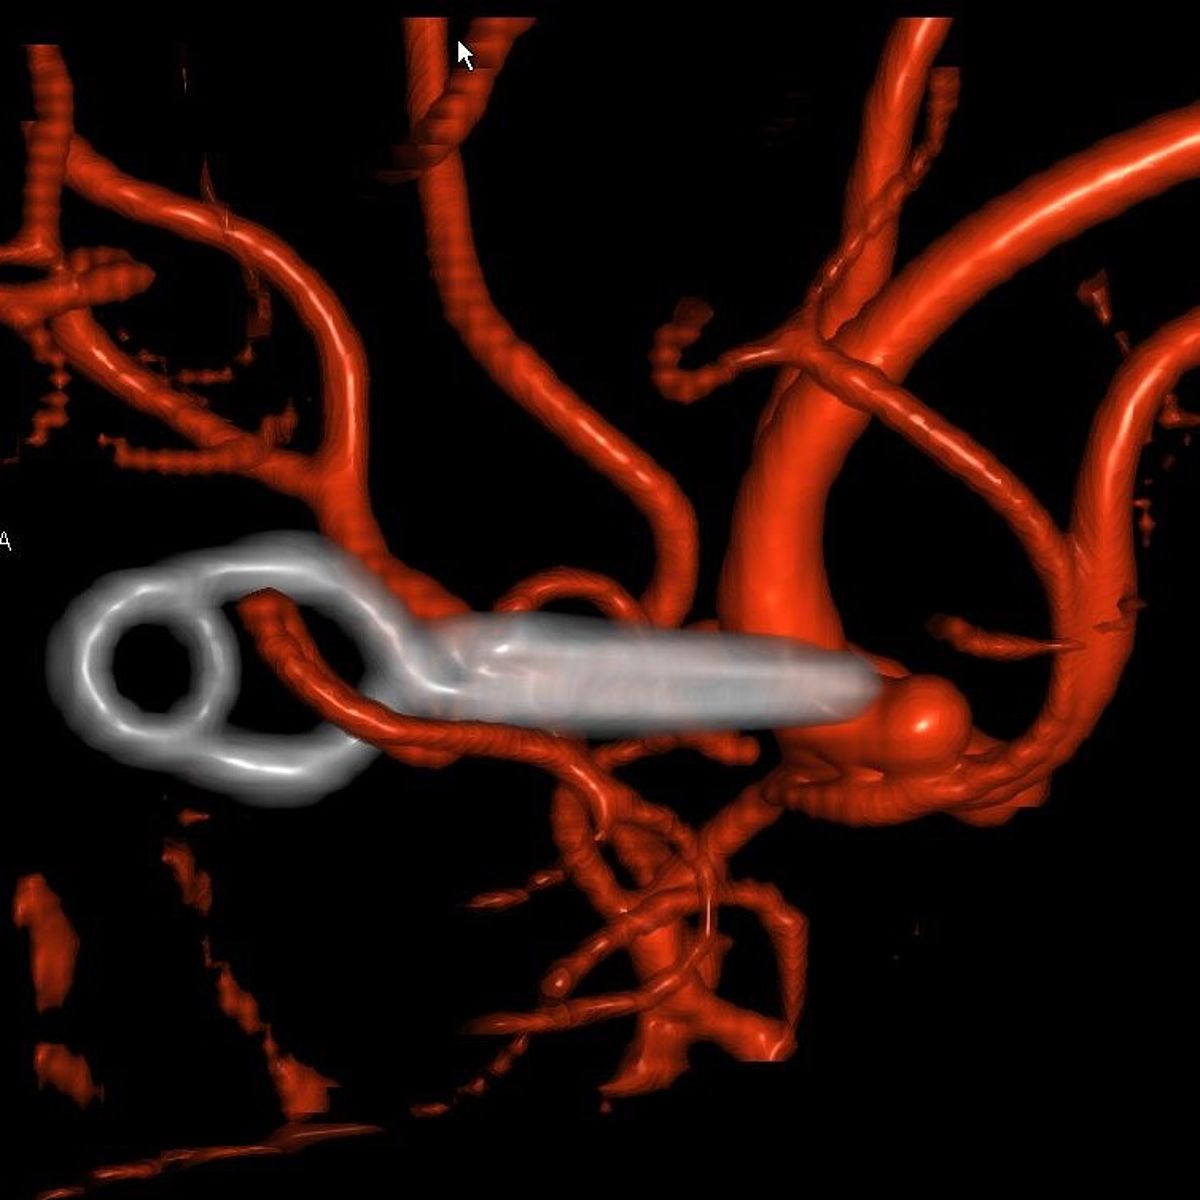

In Augsburg werden im Jahr etwa 80 solcher akuter Subarachnoidealblutungen behandelt. Dabei ist neben der Behandlung der Blutungsfolgen vor allem die Ausschaltung des ursächlichen Aneurysmas dringlich, was meist interventionell durch die Neuroradiologie erfolgt.

- Wie kann es behandelt werden?